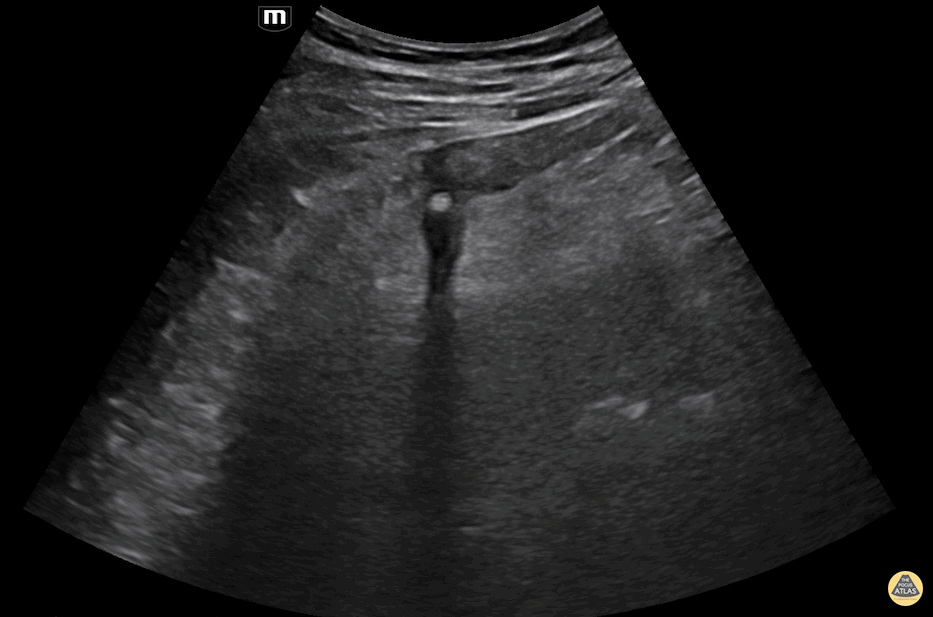

60 year old man presenting with left lower quadrant pain and fever. POCUS was performed and revealed a thick-walled colon and associated diverticula with surrounding hyperechoic fat stranding. Inside the pouch there's an echogenic structure casting deep shadowing consistent with a fecalith. Alessandro Lena